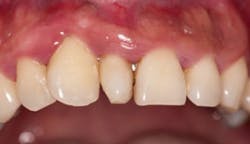

The image depicted here is one of what is termed a supernumerary tooth. In this case, it is called a mesiodens (see Figure 1). Supernumerary teeth are in excess of the normal number of teeth, and they are further classified according to their location.

A mesiodens is a supernumerary tooth in the maxillary anterior incisor region. If the supernumerary tooth were found in the posterior region it would be termed a distomolar or distodens (4th molar). If the tooth happens to be found lingually or buccally, the term paramolar is used (see Figure 2). Developmental alterations can occur affecting the number of teeth, the size of teeth, the shape of teeth, and the structure of teeth.